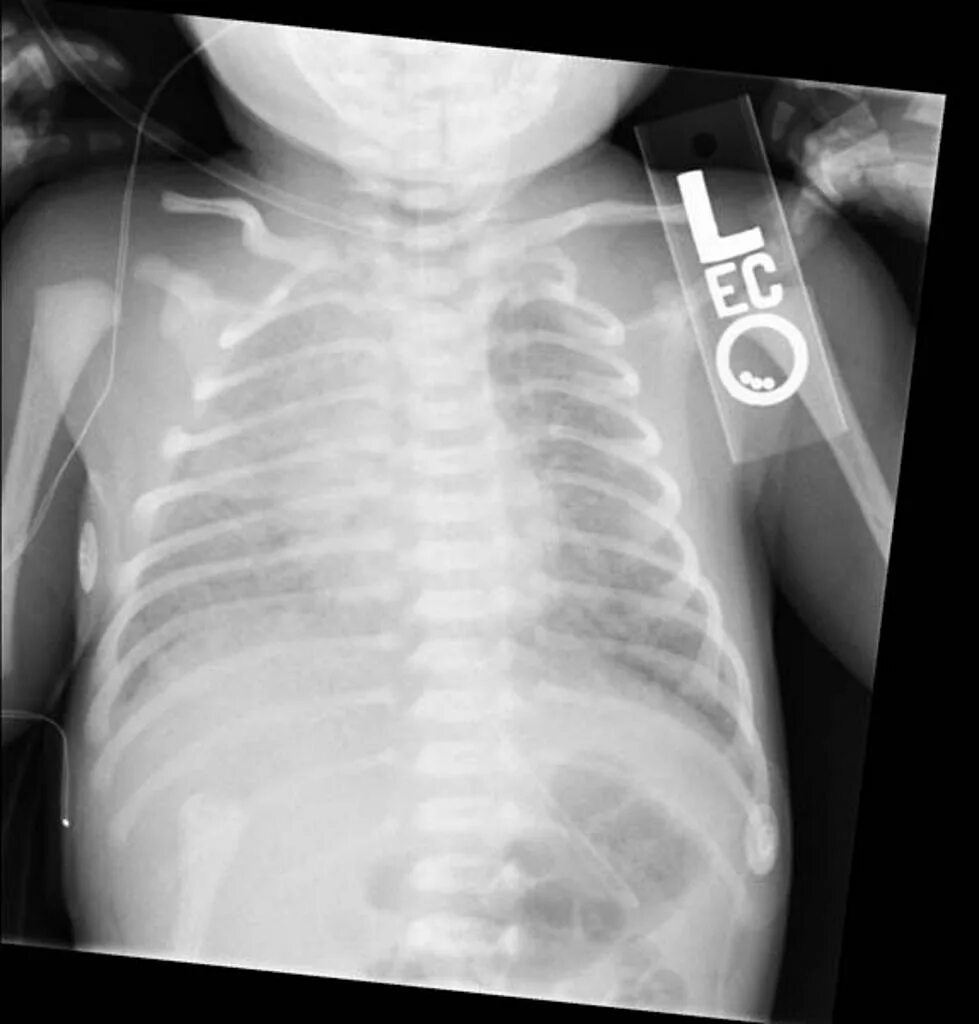

Синдром аспирации